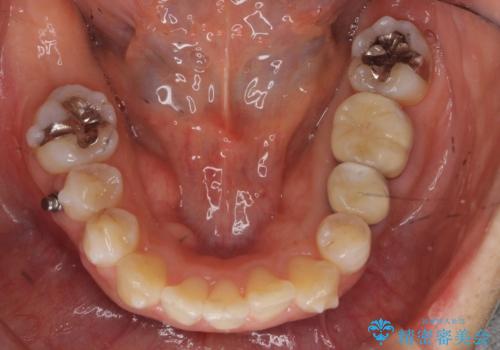

奥歯を後ろに下げて、前歯を並べています。

マウスピースと矯正用のミニスクリューを使用して治療しています。

銀歯も白くということでしたので虫歯治療も一緒に行っています。

左上7の根の治療や左下56銀歯の治療なども行いました。

右下7は根管治療をおすすめしましたが、患者様のご希望により抜歯となり、そのスペースを利用して下の前歯をならべています。